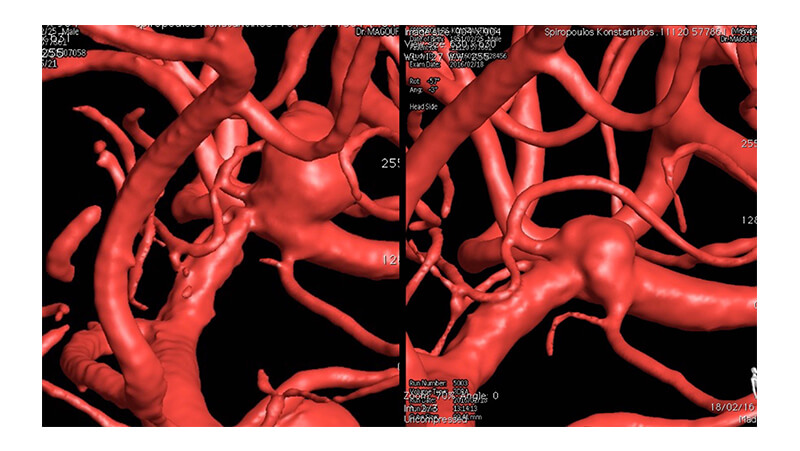

Εικόνα 2: Τρισδιάσταση ανασύνθεση εικόνων περιστροφικής ψηφιακής αγγειογραφίας. Φαίνεται ότι από την βάση του ανευρυσματικού σάκκου εκφύεται μετωπιαίος κλάδος. Η πλήρης απόφραξη του ανευρύσματος θα οδηγήσει σε απόφραξη του μετωπιαίου κλάδου. Αμέσως πριν το ανεύρυσμα, στο τελικό Μ1 τμήμα, διακρίνεται η τοπική στένωση της μέσης εγκεφαλικής αρτηρίας.